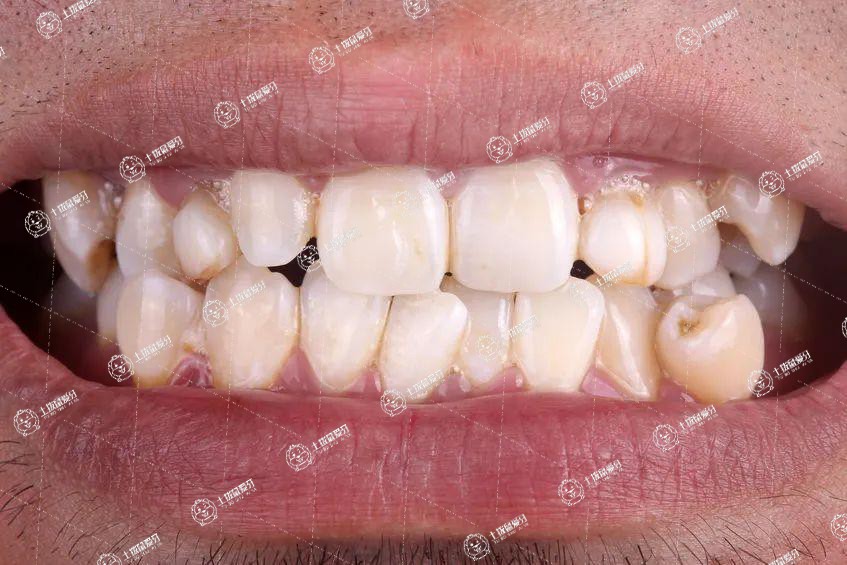

牙齒擁擠可以說是很多牙友們常常會面臨的牙齒問題,當(dāng)牙友們出現(xiàn)畸形牙齒后往往不僅影響美觀,還可能引發(fā)口腔疾病。因此,不少父母在了解到這一情況后都會選擇及時給孩子做矯正牙齒,牙齒擁擠不拔牙可以矯正嗎?一起來了解一下。

牙齒擁擠需不需要拔牙,這是需要根據(jù)患者的牙齒擁擠的情況來看的。如果牙齒擁擠的程度比較嚴(yán)重,使矯正的位置不夠,則需要進(jìn)行拔牙來留出矯正的空隙。拔牙是為了使牙齒上下左右的協(xié)調(diào)性對稱,不會影響到牙齒的美觀、功能和健康。如果是有空隙矯正,則只需要進(jìn)行牙齒矯正就可以。所以,患者的牙齒矯正是否需要拔牙,需要患者到正規(guī)的牙科醫(yī)院進(jìn)行檢查才能來判斷。